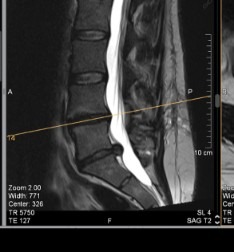

Hi my name is Mike, my best friend Carly who is 31 needs artificial disc replacement surgery for 2 discs. First is the disc between L4/L5, the second is between L5/S1. She has had back pain for quite a few years and in April 2025 her disc between L5/S1 herniated so bad that it took walking and she went in for a discectomy in August 2025 and afterwards had hope of no pain but a week and a half later the same disc re-herniated.